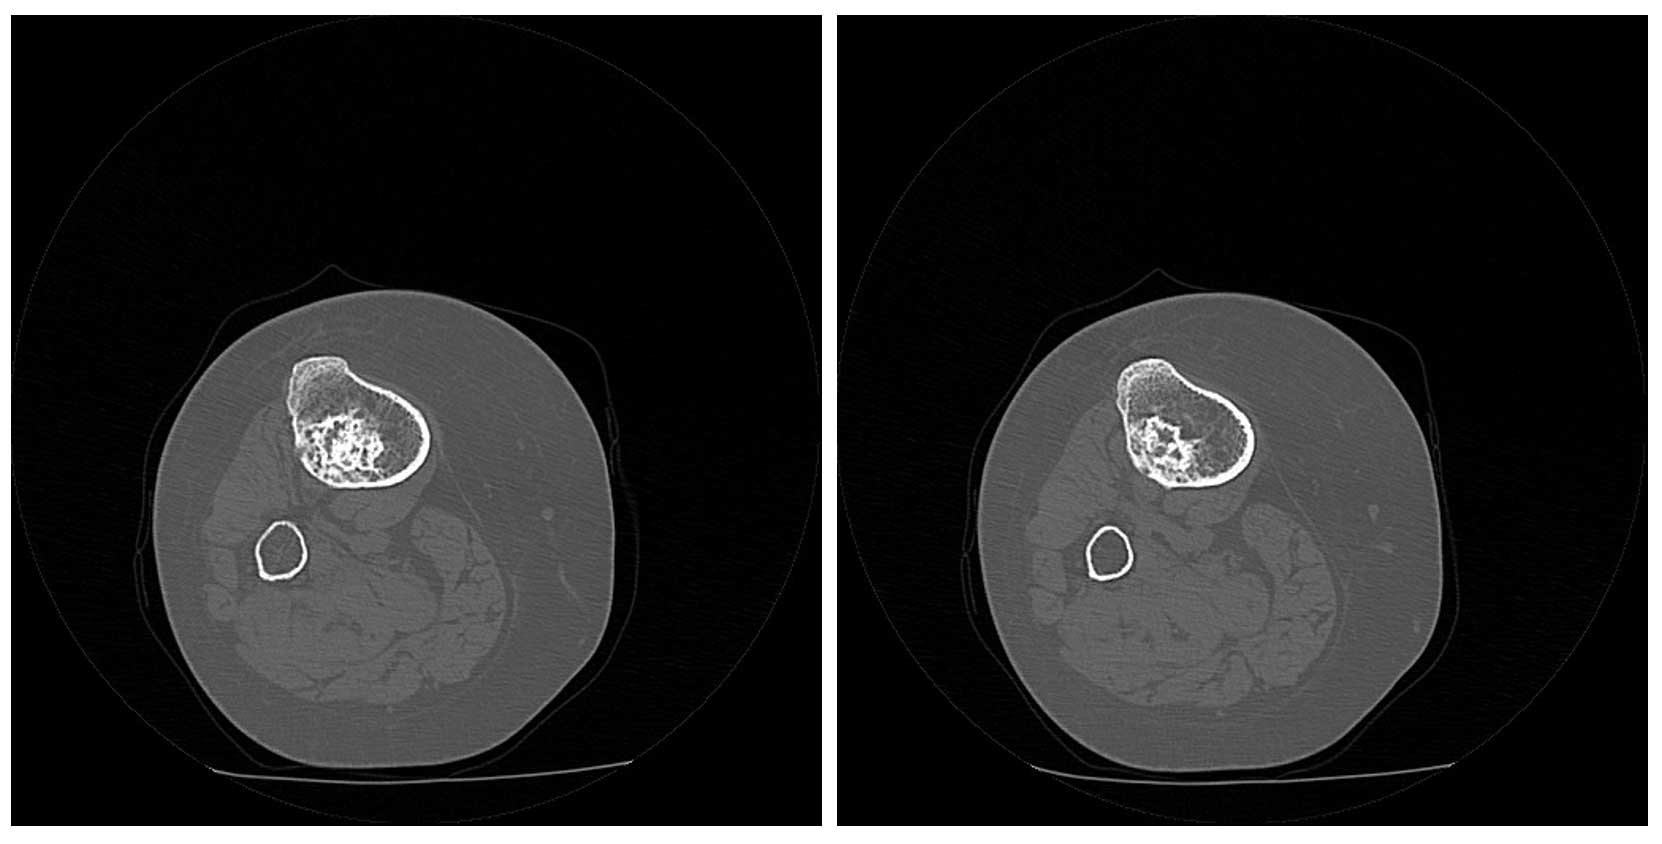

Ameliyat Öncesi: Tomografide kıkırdak içerik ve kortekste düzensizlik görülmekte.